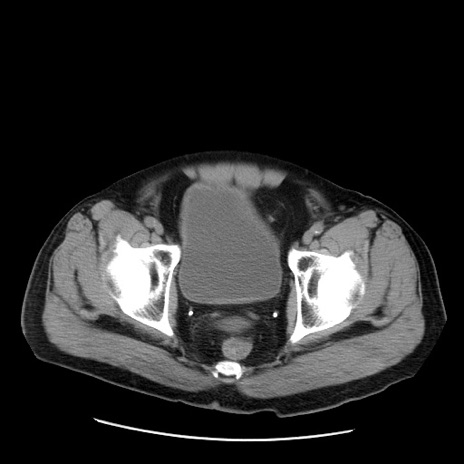

症例20(横断像)

【症例】 60歳代男性

【主訴】 腹部膨満、嘔吐

【現病歴】5日前頃より倦怠感を認め食事量減少し4日前の朝嘔吐、食事摂取困難となった。 3日前近医受診し点滴施行され整腸剤などを処方された。 当日他院を受診し、腹部膨満著明、炎症反応の上昇(CRP10.8、WBC11200)あり、紹介受診となる。

【身体所見】 意識JCS1 受け答えがはっきりしないBP 111/57mHg、 P 67bpm、、BT35.2°C、SpO2 97%(RA)、 腹部:膨隆、打診で鼓音あり、全体的に圧痛有り、腸蠕動音(-)、反跳痛ははっきりせず。

【データ】WBC 11400、CRP 14.20